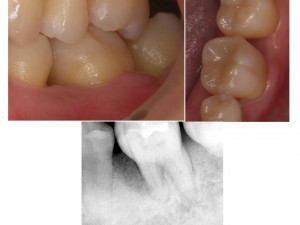

歯科受診がお久しぶりで、クリーニングをご希望された患者様の口腔内写真です。

歯石と、喫煙による歯の着色が目立ち、ご本人も気にされていました。

歯石除去とエアフローでクリーニングを行いました。

その後、歯周病の検査により、軽度の歯周病の進行を認めた為、歯周治療も行いました。

歯周治療により、歯肉の改善を認め、

さらに審美的に歯肉着色を改善する為に、歯肉ピーリングを行いました。